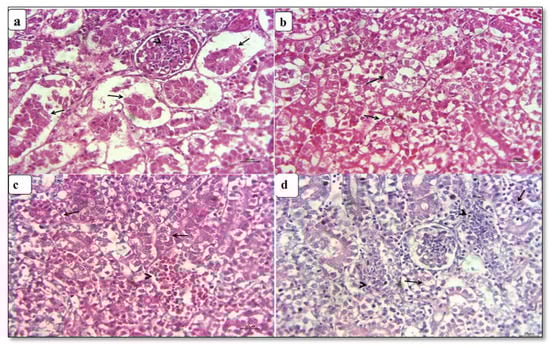

3.4. Histopathological Findings